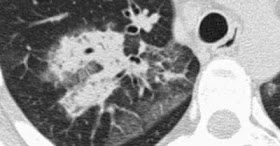

Here we see consolidation and ground-glass opacity in a patient with persistent

chest abnormalities and weight loss without signs of infection.Not suprisingly, there is a big overlap in the causes of ground-glass opacity and consolidation and some diseases may present with both areas of ground-glass and consolidation.

This suggested a chronic disease.

There is no honeycombing or traction bronchiectasis, so we can rule out fibrosis.

The weight loss is suggestive of a malignant disease.

Histology revealed broncho-alveolar cell carcinoma

Broncho-alveolar cell carcinoma

(BAC) may present as:

- solitary nodule or mass (40% of patients)

- focal or diffuse consolidation (30%) as in this case.

- diffuse ill-defined centrilobular nodules (30%) due to

endobronchial spread.